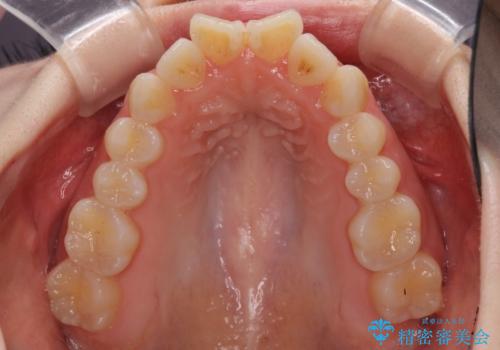

- 前歯の捻れと、ちょっとした出っ張りを気にして来院された患者様です。

歯と歯の間を削る(IPR)ことでデコボコを解消し、インビザラインで整えることとしました。

インビザライン治療特有の奥歯が接触しない時期が続き、当初予定よりも期間がかかりましたが、最終的には安定した咬み合わせと、整った前歯になりました。